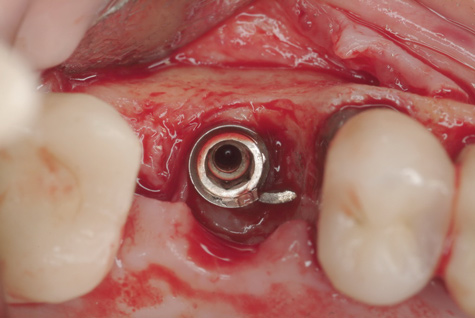

(7.) Because apical and lateral bone volume was preserved with use of an ultrathin trephine, a wider diameter, 4.2-mm implant was placed at the time of implant removal. Bone augmentation was performed, and submerged healing was selected.

Figure 7